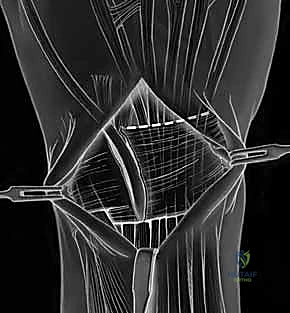

- Ligament-Splitting Capsulotomy: We'll perform a dorsal ligament-splitting capsulotomy, as described by Berger and Bishop. This approach is preferred because it preserves the integrity of the crucial dorsal radiocarpal and intercarpal ligaments, which are important secondary stabilizers.

- Identify Key Ligaments: First, identify the dorsal radiocarpal ligament (specifically the dorsal radiotriquetral ligament) and the dorsal intercarpal ligament. These form a "V" shape on the dorsal aspect of the wrist.

- Incision: The capsulotomy incision is made between these two ligaments, splitting the capsule longitudinally.

TECH FIG 5 • A. Dorsal ligament-splitting capsulotomy planned.

TECH FIG 5 • B. Dorsal ligament-splitting capsulotomy showing location of the dorsal radiotriquetral and scaphotriquetral ligaments.

* Reflection: Carefully reflect the dorsal capsule radially and ulnarly, creating two flaps. Use fine stay sutures or small skin hooks to retract the capsule, providing excellent visualization of the underlying carpal bones and ligaments.